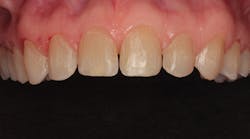

In 2016, she decided that she wanted to replace her veneers with the new bleach-shaded materials available today. In Figure 1, you can see her veneers as they appeared after nineteen years. Note the excellent tissue health and minimal tissue recession. There was a small fracture in the disto-incisal corner of the right central incisor. The incisal view at this date can be seen in Figure 2.

Figure 1: The patient’s porcelain laminate veneers placed in 1997 as seen in 2016